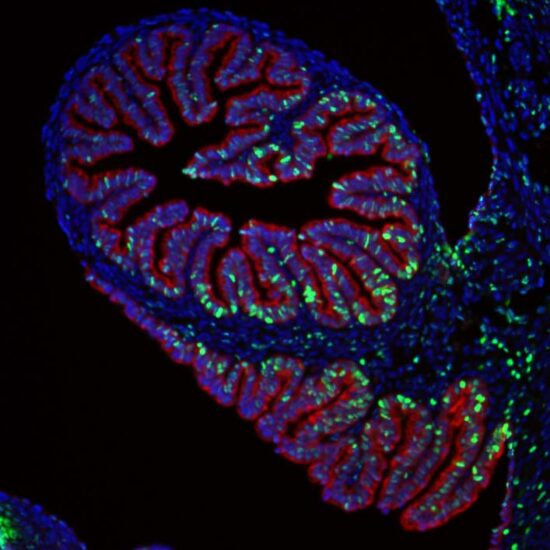

Dr. Amrita Salvi looks onto mouse derived fallopian tube cells exposed to BPA through a fluorescence microscope